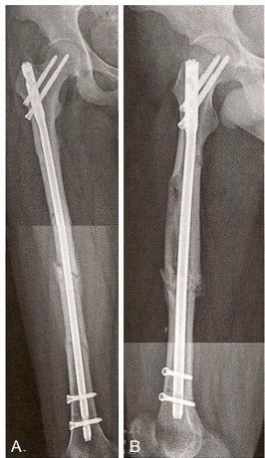

(6)术后3个月随访,示骨痂明显生长(图12-7)。

图12-7 术后3个月X 线片。A.正位片;B.侧位片